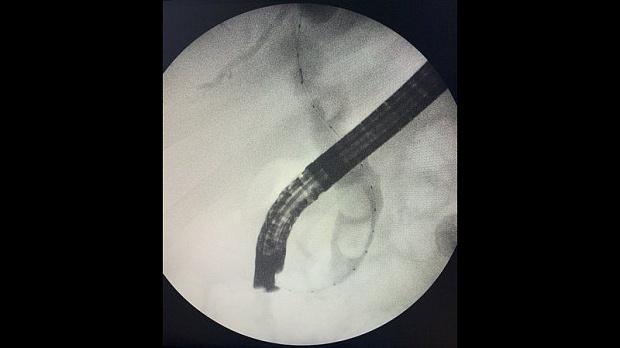

Отмечатся юкстапапиллярное расположение большого дуоденального сосочка тип-3. Канюляция папиллотомом pull-type ,контрастирование водорастворимым контрастом .

Рентгенологическая картина расширенния желчных протоков и наличие конкрментов в холедохе. Произведена эндоскопическая ограниченная папиллосфинктеротомия, отмечалось поступление темной желчи. Ревизия корзиной Дормия дали основания полагать ,что конкременты плотной консистенции.

Учитывая состояние пациента, большой степени вероятности осложнений и наличие крупных конкрементов в холедохе , принято решение следовать общепринятой тактике лечения при юкстапапиллярном расположении БДС - воздержаться от одноэтапного проведения операции с литэкстракцией. Произведено стентирование холедоха пластиковым стентом типа Pig-tail 10 Fr-130 мм, чем достигнуто адекватное дренирование желчных путей. Послеоперационный период протекал без осложнений. Биохимический анализ крови: билирубин общий-17.0 , билирубин прямой -13.0 , билирубин непрямой - 4, с-реактивный белок -24.3, скорость клубочковой фильтрации-37,4. По представленным результатам обследования в послеоперационом периоде, можно отметить положительную динамику в показателях пигментного обмена. Пациент в удовлетворительном состоянии выписан на амбулаторное лечение .